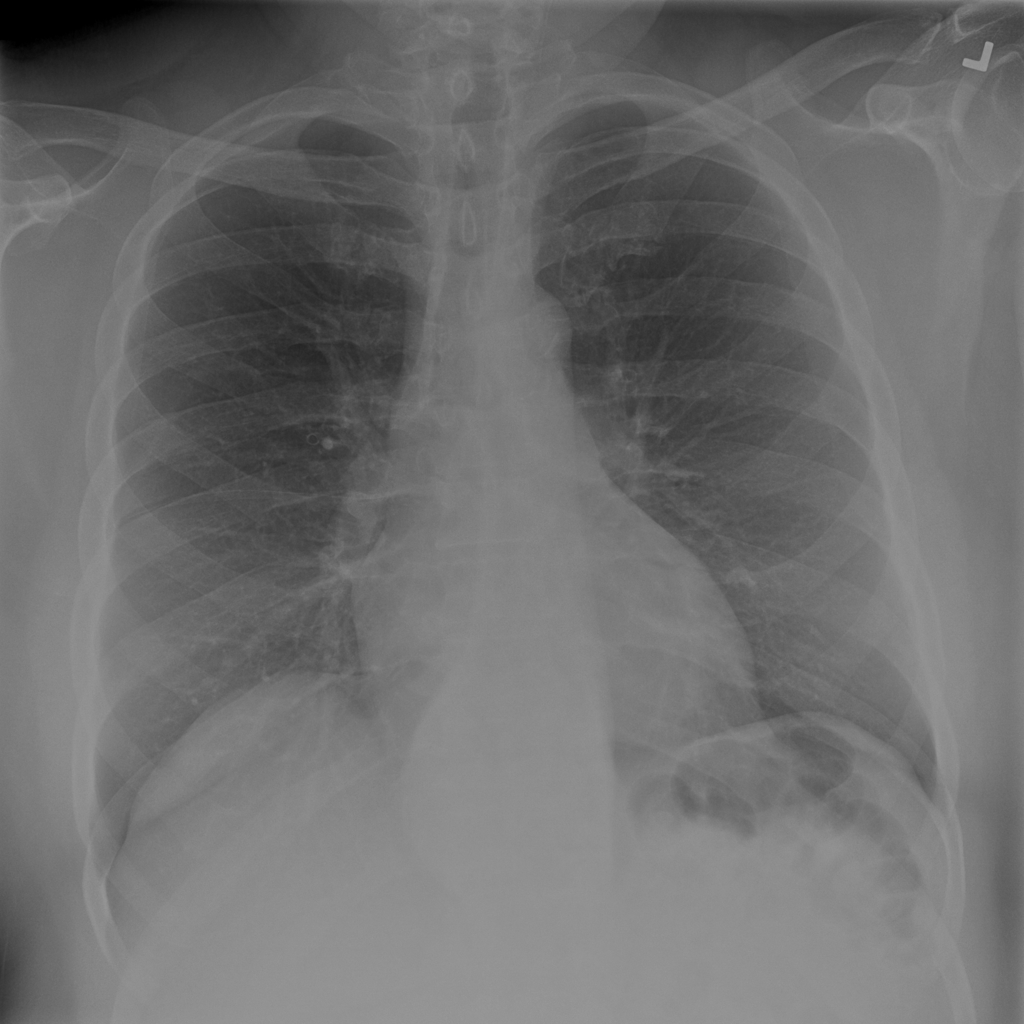

Showing up to 90 reference images for Hernia.

PAT-C048 · IMG-001Hernia

PAT-C048 · IMG-001

PA